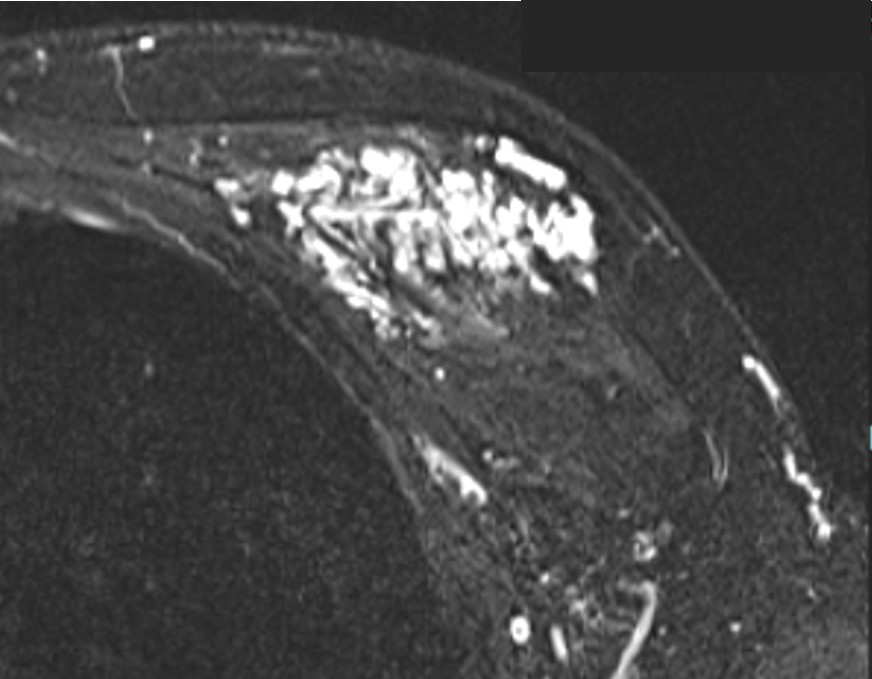

1.初診時(生後0か月)

2.初診から1か月後、増大傾向でレーザー治療開始

3.初診から4か月後、増大傾向が強く内服治療開始

4.内服開始6か月、ほぼ消退しており治療終了